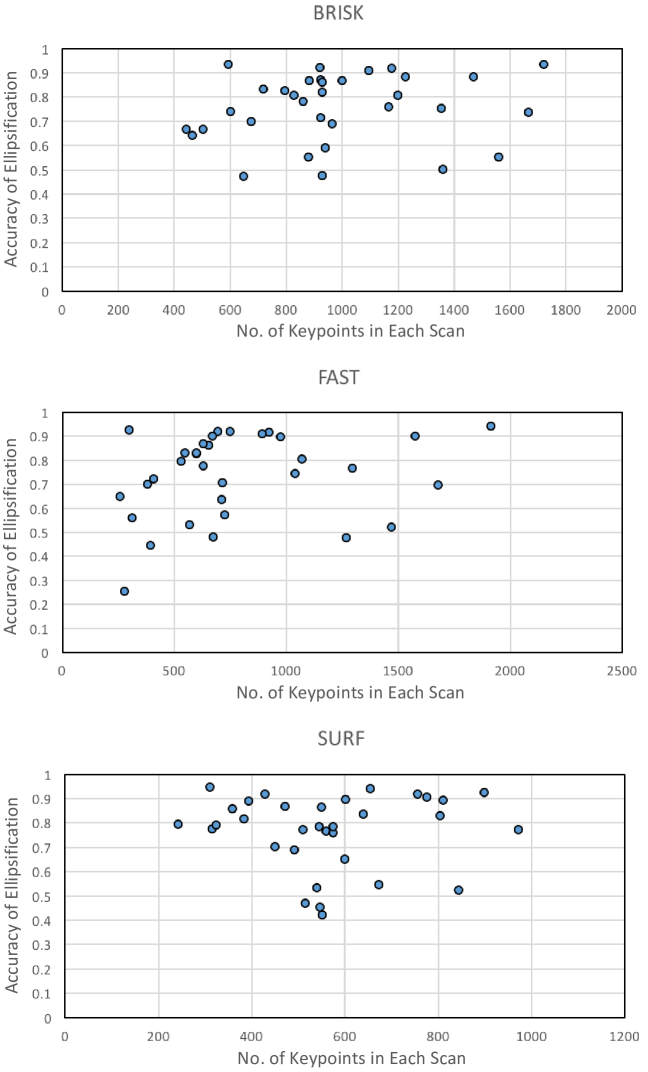

Fig. 3 shows the distribution of the accuracy of ellipsification in respect to the number of generated keypoints for all the images used in the experiments (the results are only shown for the SVM classifier). BRISK, with an average accuracy of 75.63%, produced keypoints. FAST, with an average accuracy of 73.66%, resulted in keypoints. And SURF, with an average accuracy of 76.65%, generated keypoints. Therefore, the SURF achieved a higher performance using a smaller number of keypoints, which reduced the computational cost of subsequent classification step. Moreover, the SURF was more consistent in selecting the number of keypoints from B-mode images, as can be judged from the smaller standard deviation (179) achieved compared to the other two methods.